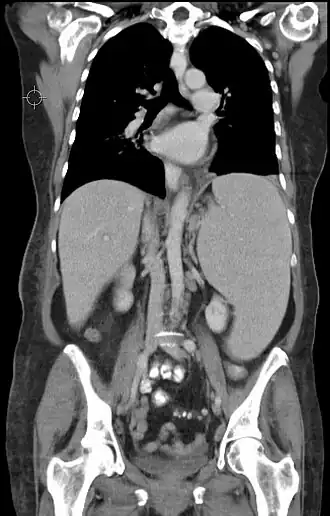

![]() | |

| Medula óssea de uma pessoa com leucemia linfoblástica aguda de percursores B. Coloração de Wright | |